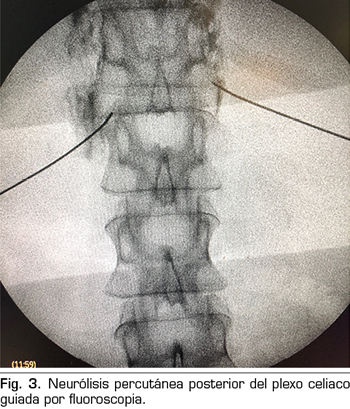

– Abordaje transcrural: el más utilizado para el bloqueo del plexo celiaco (Figura 3). El paciente se coloca en decúbito prono, identificando el cuerpo vertebral L1 y avanzando una aguja por cada lado, a unos 7,5 cm de la línea media, hasta atravesar la crura diafragmática y bloquear el plexo.

Consiste en la destrucción de las fibras que componen el plexo celiaco mediante la inyección de un agente neurolítico, prefiriéndose el uso de alcohol debido a su menor afinidad por los vasos sanguíneos, comparado con el fenol. El abordaje clásico más utilizado es el transcrural bilateral por vía posterior, guiado por fluoroscopia o TAC.